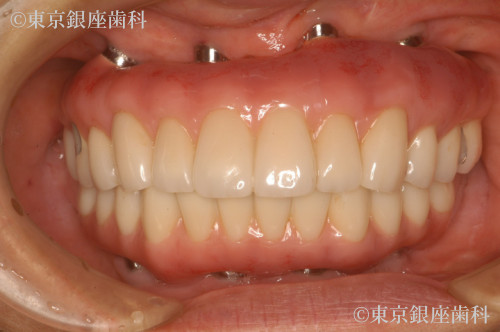

長年の入れ歯生活から自分の歯のように噛める喜びを取り戻した50歳代男性のインプラント症例

若い頃から入れ歯を使用し噛めない・笑えない悩みを抱えていたが、上下インプラントで噛み合わせと表情が改善。再手術も経て安定している。

上下ワンデイインプラント(再オペあり)